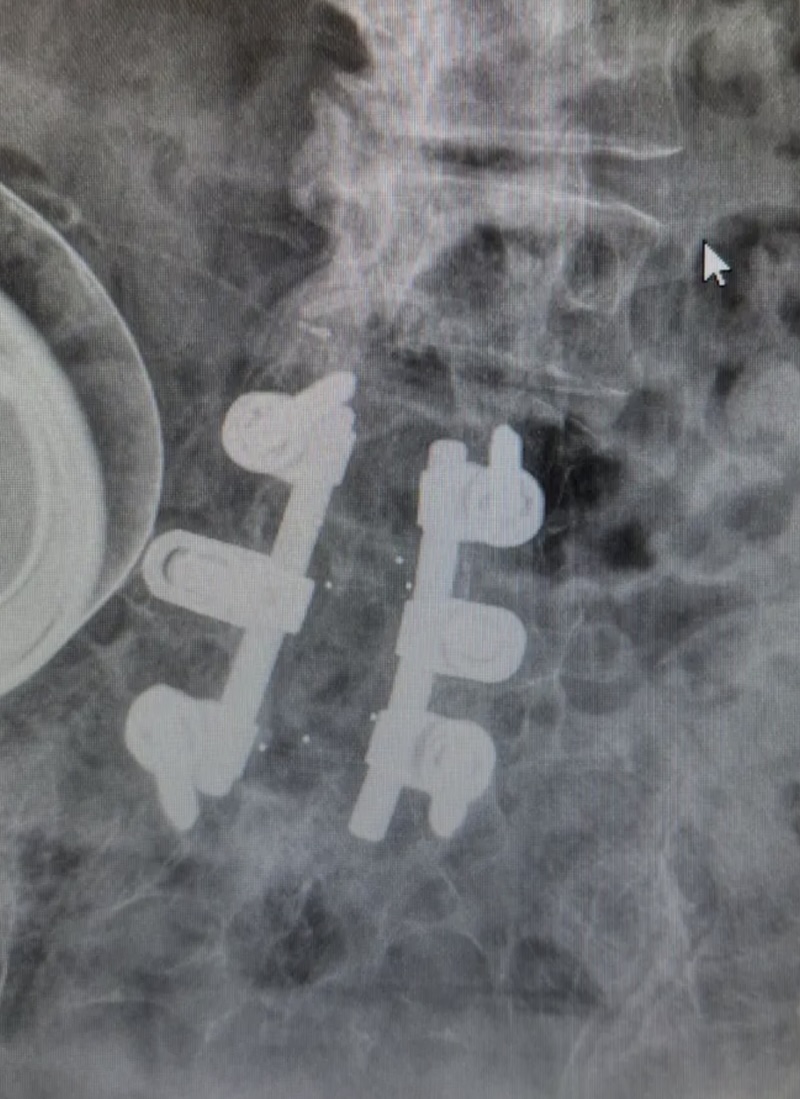

DePuy Monarch Offset Pedicle Screw System (Historical)

Features: Detachable/ Modular Head , Polyaxial Head , Fixed Head

The MONARCH Spine System was originally produced by DePuy and is a titanium thoracolumbar pedicle screw fixation system. It is characterized by the pedicle screw with a polyaxial offset plate.

• Secured by 8mm (9/16 will work) Hexagonal nut

• Washer below hex nut

• Offset connector below washer

• Offset connector to rod is 2.5mm female hex nut

• X T20 star screw driver used to remove the actual pedicle screw shank